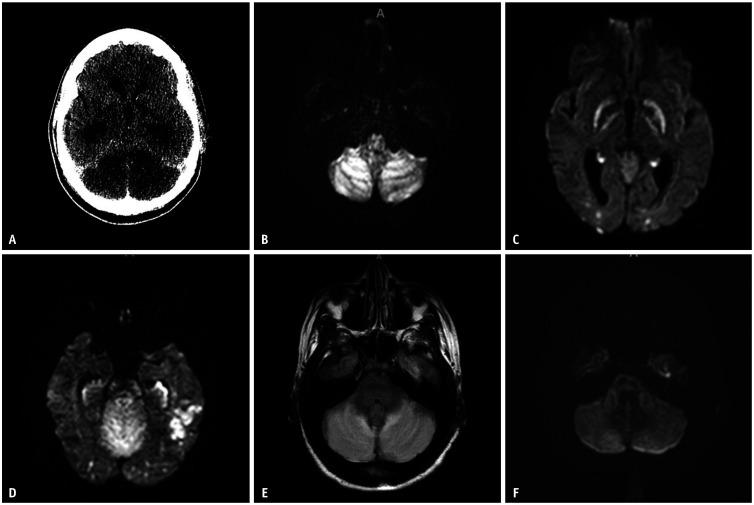

Cerebellar, Hippocampal, and Basal Nuclei Transient Edema With Restricted Diffusion (CHANTER) Syndrome: Radiologic Features and Findings.

Korean J Radiol. 2024 Mar;25(3):314-318. doi: 10.3348/kjr.2023.1142.